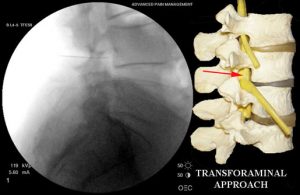

space behind the disc and is felt to be an older less direct approach. For this reason, this approach is used less often in the lower back but more often in the mid back and neck. - Transforaminal ESI or retro-discal ESI: with this ESI approach the spinal needle is placed into the foramina or opening for the nerve root on the same side of the spine as your pain and at the same level. Using X-ray guidance to steer the needle the Transforaminal approach directs the needle above the exiting nerve root and the retro-discal approach directs the needle below the exiting nerve and directly beh

ind the disc at the affected lumbar level. These 2 approaches are felt to be the most direct way to deliver the medication to the problem area. When done correctly, they can work quickly to alleviate pain and are generally very safe. While these approaches are considered therapeutic they can also provide diagnostic information and when this is done we call it a selective nerve root block. Transforaminal ESIs can be performed in the neck, mid-back and lower back.